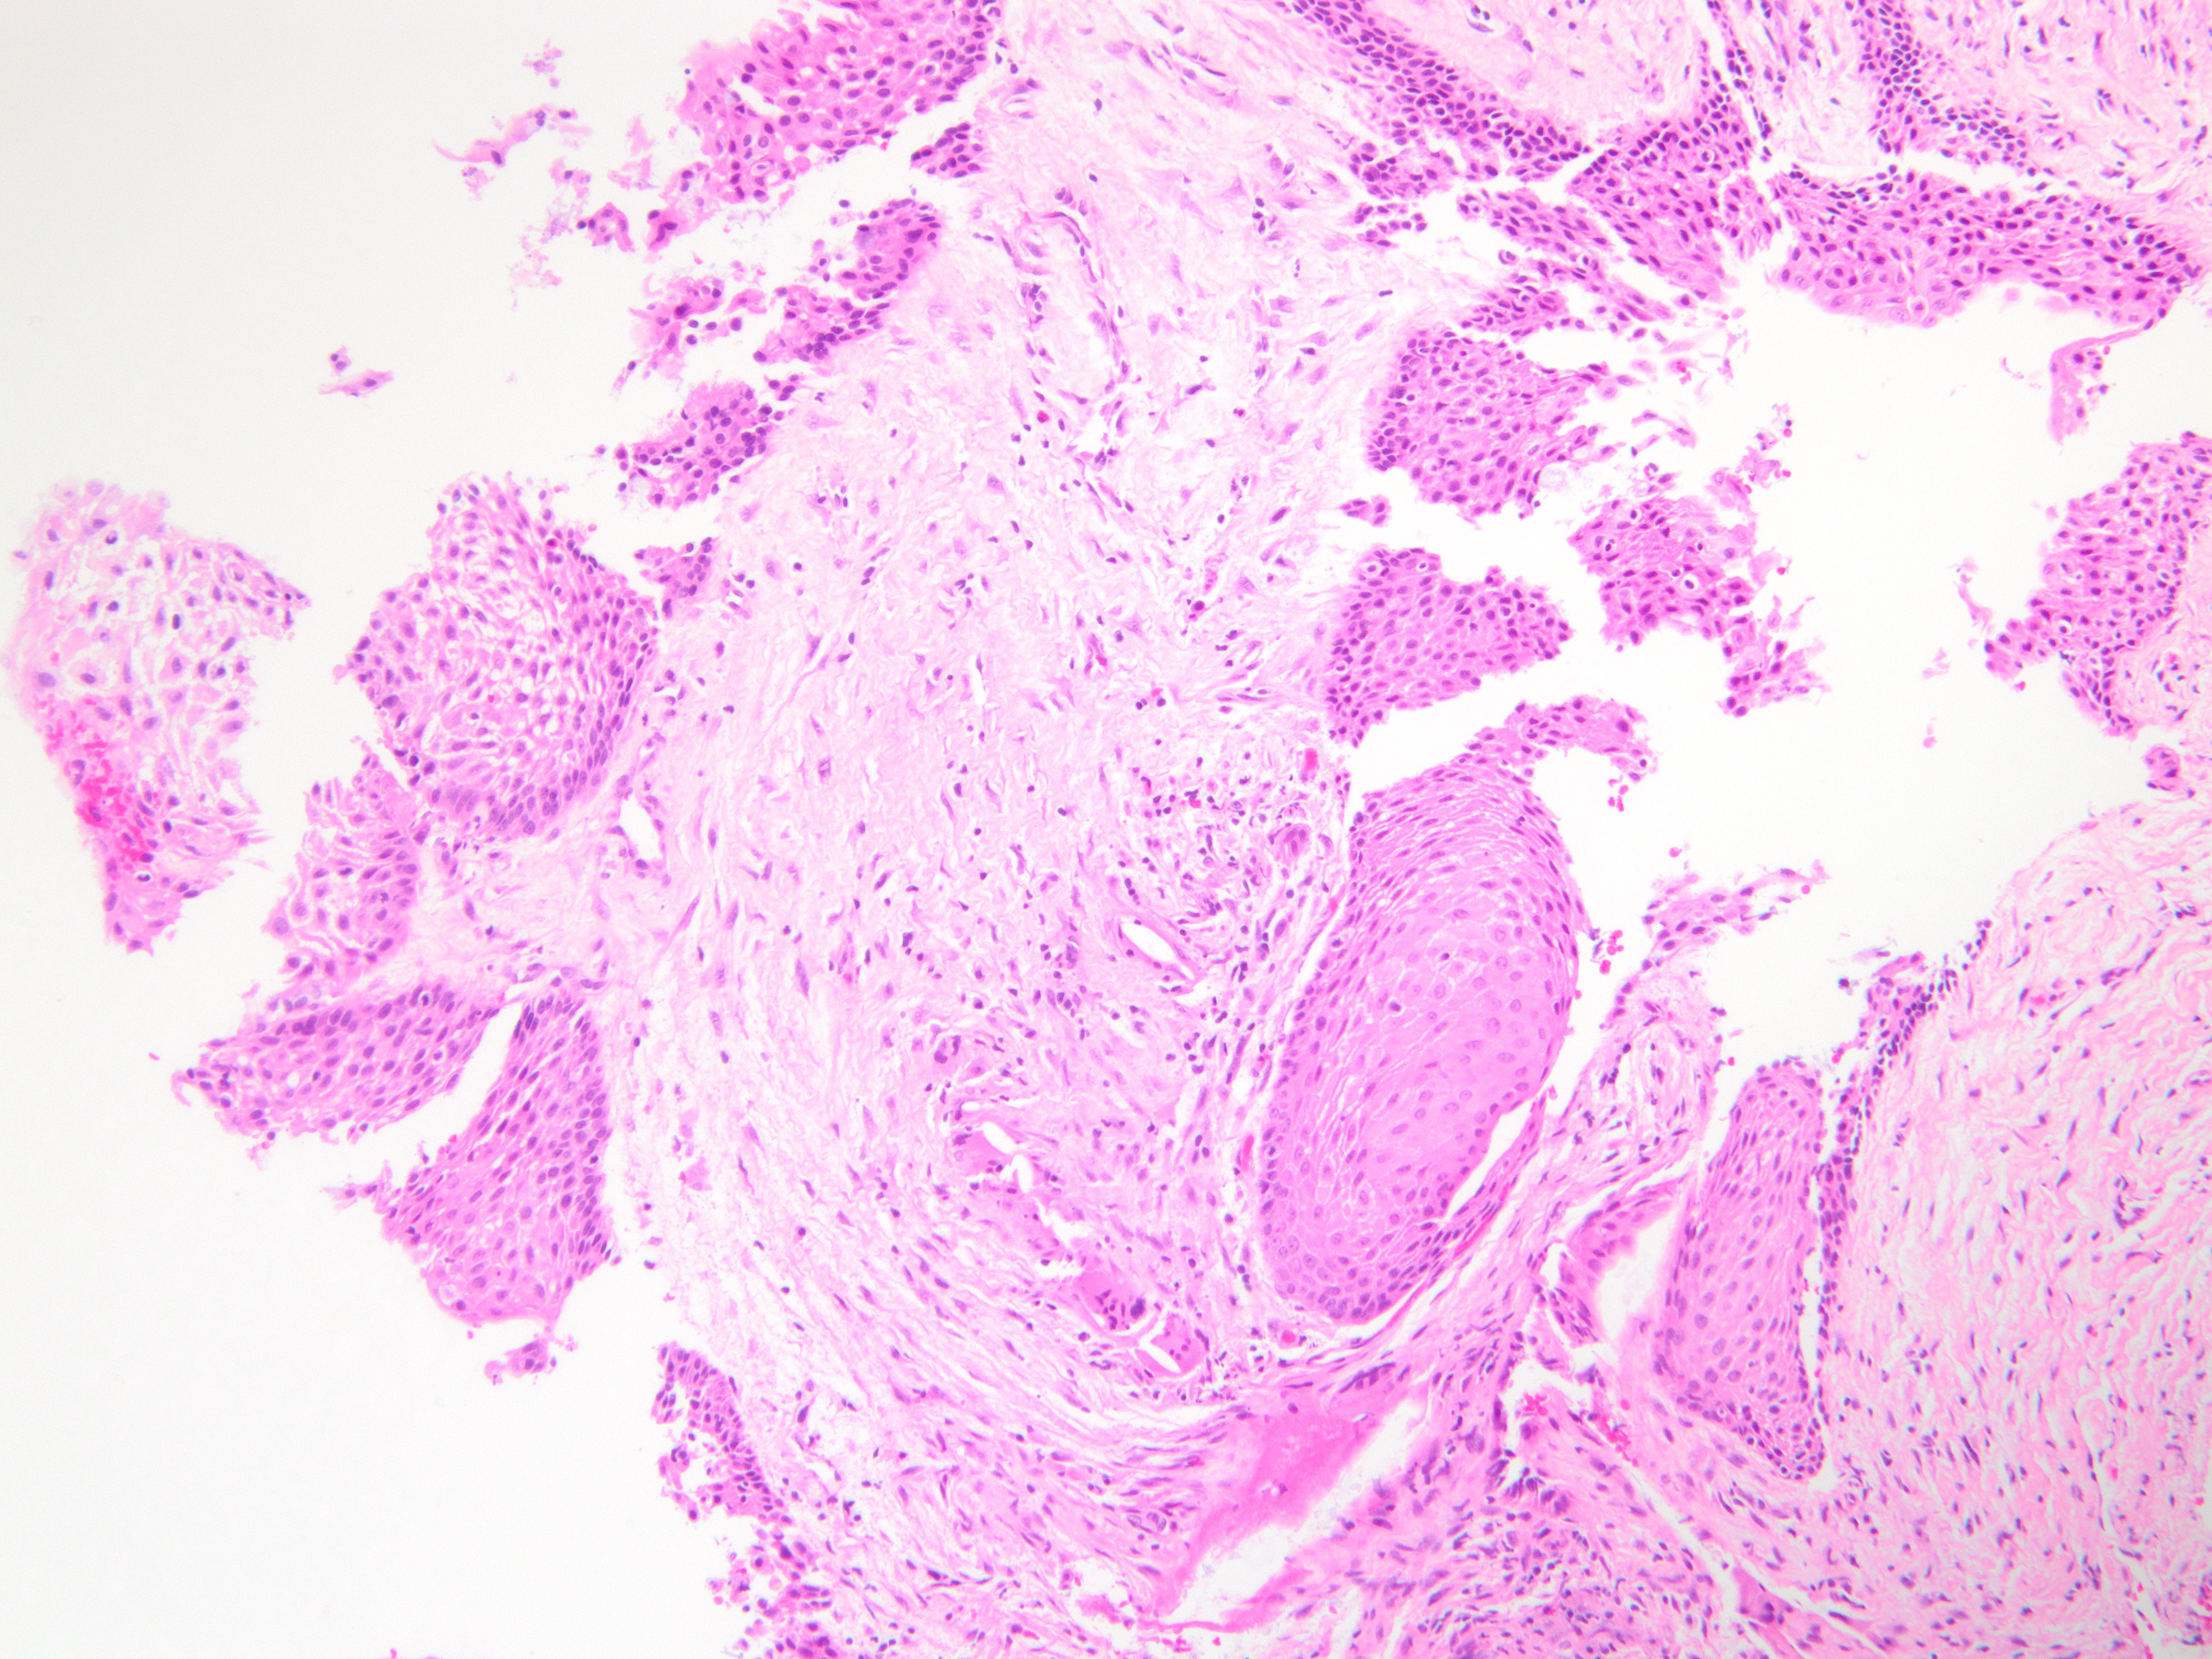

Brief explanation of the answer: Sections show cyst lining of variable thickness with mucous cells, ciliated cells, eosinophilic cuboidal cells, and clear cells. There are multiple compartments. Microcysts, papillary projections and epithelial spheres are present. These features are consistent with glandular odontogenic cyst. Resection is recommended due to high recurrence rate.

No basal cell palisading or parakeratin is noted, excluding odontogenic keratocyst. Periapical and radicular cysts tend to have a squamous lining with abundant inflammation. Mucoepidermoid carcimoma tends to be more proliferative with invasive features, and also shows intermediate and epidermoid cells.